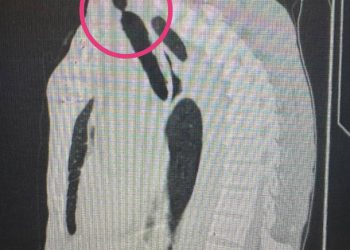

Врачи Республиканской клинической больницы помогли 41-летней жительнице Набережных Челнов удалить множественные миомы, сохранив матку. Об этом рассказали в пресс-службе клиники. ...